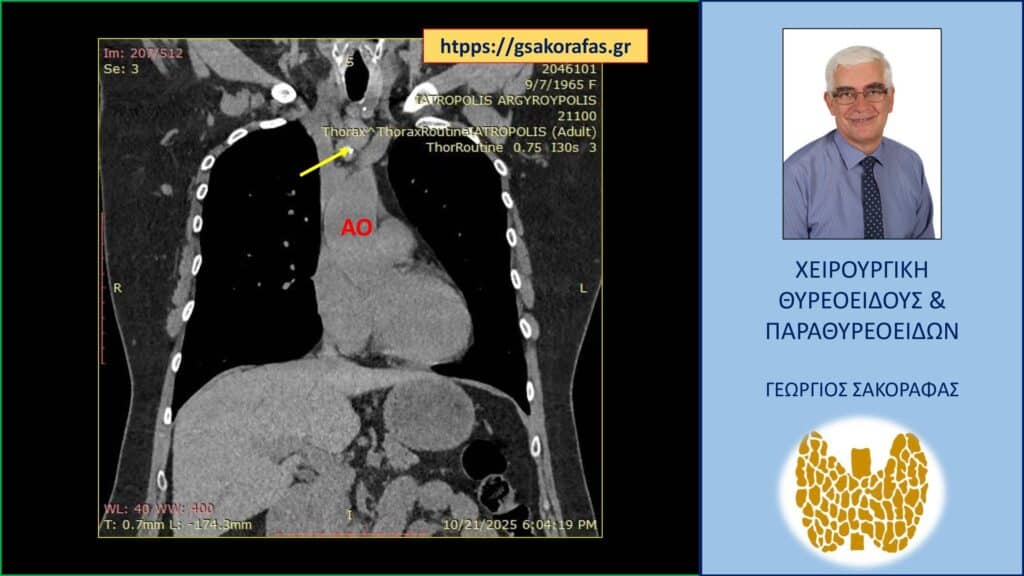

- Γιατί είμαστε σε θέση να εκτελέσουμε με ασφάλεια και αποτελεσματικότητα κάθε είδους χειρουργική επέμβαση θυρεοειδούς – παραθυρεοειδών, ακόμη και σε επιπλεγμένα (δύσκολα) περιστατικά, όπως εκτεταμένοι λεμφαδενικοί καθαρισμοί σε καρκίνο θυρεοειδούς, επεμβάσεις σε λίαν ευμεγέθεις καταδυόμενες στο μεσοθωράκιο βρογχοκήλες, υποτροπές παθήσεων θυρεοειδούς (συμπεριλαμβανομένου του καρκίνου θυρεοειδούς), υποτροπές υπερπαραθυρεοειδισμού, αδενώματα παραθυρεοειδών σε έκτοπη θέση ή λόγω υπεράριθμων παραθυρεοειδών, διάχυτη υπερπλασία παραθυρεοειδών, κλπ.